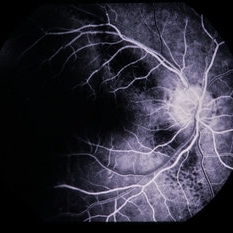

Choroidal Melanoma

Apr 11 2014 by David Callanan, MD

68-year-old white male, choroidal melanoma.